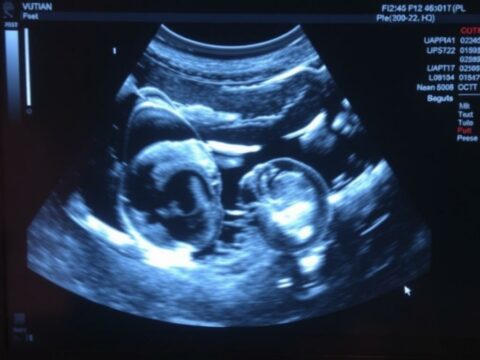

УЗИ яичников: что именно смотрят врачи, как подготовиться и как не испугаться результата

УЗИ яичников — название знакомое многим, но не все понимают, что именно происходит во время исследования и какие выводы по… read more УЗИ яичников: что именно смотрят врачи, как подготовиться и как не испугаться результата